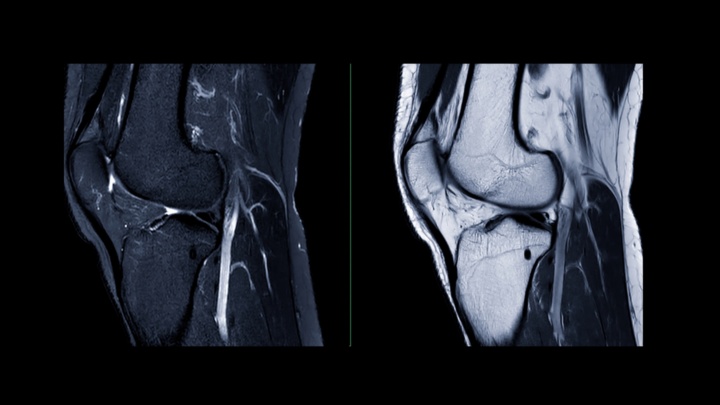

Magnetska rezonanca koljena neinvazivna je dijagnostička pretraga koja pomoću snažnog magnetskog polja i radio valova stvara detaljne slike unutarnjih struktura koljenskog zgloba.

MR koljena omogućuje liječnicima precizan uvid u kosti, hrskavice, ligamente, tetive i okolna meka tkiva koljena. Visoka rezolucija MR snimki može pokazati i vrlo sitna oštećenja te tako pomoći odlučiti treba li, primjerice, operativni zahvat.

Pretraga se najčešće radi kako bi se utvrdio uzrok bolova, otoka ili nestabilnosti u koljenu koji se ne mogu jasno dijagnosticirati drugim metodama.